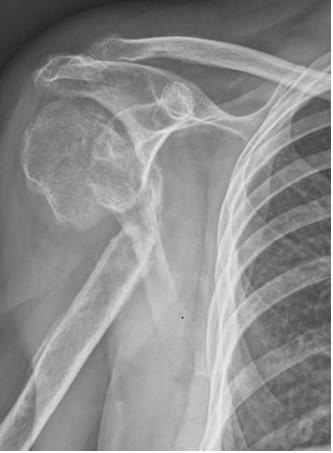

A 69-year-old woman came to ER of Poliambulanza of Brescia in October 2019. X-rays were obtained. Fracture involved proximal humerus of the right, dominant, upper arm. The fracture was 11C3.1 according to AO classification. At first, the fracture was treated with an external. fixation using a Galaxy EF in the first twenty-four hours. The EF was removed after one month because of the loss of reduction with displacement of the fracture. Physio- kinesitherapy was indicated but she was unable to underwent to treatment. She was lost at follow -up for several months due to COVID-19 pandemic and the social limitations that resulted. After 7 months, Xrays showed a dislocated nonunion of proximal humerus with necrosis of the head. She complained shoulder pain with passive elevation of 40° and scapular dyskinesia. In March 2021 she was listed for a reverse shoulder arthroplasty. During the surgery, Synovasure test and white blood cell count were performed: both tested negatives. A cemented trauma stem “Equinoxe” by Exactech number 8 mm was applied with a standard baseplate fixed with three screws of 26, 18, 18 mm. External rotators were reinserted, and range of motion (ROM) was good at three months follow-up.

Therefore, our choice has been to implant a reverse shoulder prosthesis with a cemented trauma stem “Equinoxe” by Exactech number 8 mm. This choice involved several compromises like technical difficulties due to the severe bone loss and higher risks of dislocations, infections, nerve injuries and thromboembolism due to the use of cement, compared to an arthroplasty with a pressfit stem [17-20]. At three-month follow-up, the patient showed no pain and a sufficient function of the joint. Since the exact amount of loss to follow-up is not valuable, there is a chance that cases of nonunion in longstanding fractures like this could increase in the near future. Our experience shows that cemented stem fixation can be an important choice of treatment for these patients. Other strategies, like telemedicine, should be considered and eventually implemented to prevent this kind of consequences resulting from the pandemic [21-23].